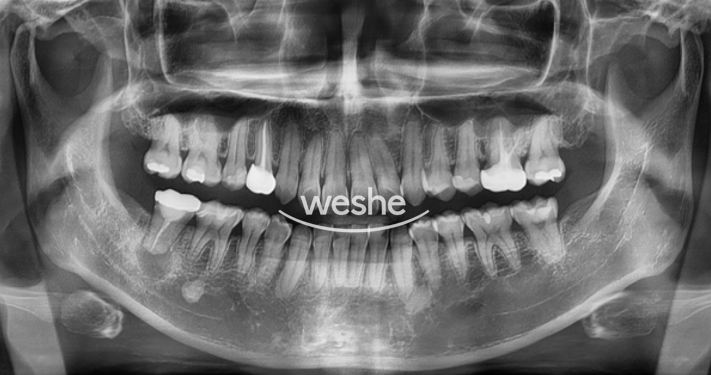

우리가 흔히 마곡역 치과 방문에서 찍는 x-ray 사진입니다.

Panorama x-ray라고 합니다.

환자는 오른쪽 아래 어금니 부위가 불편하다고 오셨습니다.

신경치료를 받고 크라운 치료까지 되어있네요. 뿌리 끝에 동그란 그림자가 보이네요.

빨간색으로 표시된 부분이 심상치 않아 보입니다.